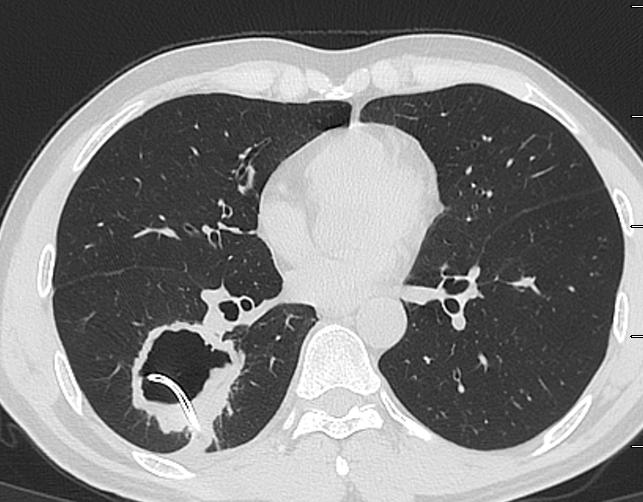

外院不知道为什么就考虑肺脓肿,还在“脓腔”里面放一大个引流管。这种骚操作,不容易见到。各位请看。

图02-05

首先,我们不得不承认,这个放引流管的水平,确实高!就像洲际导弹,准确的命中目标,引流管放在了空洞的正中央。

这个引流管放进去,啥都没有引流出来,还导致了少量气胸。

图06